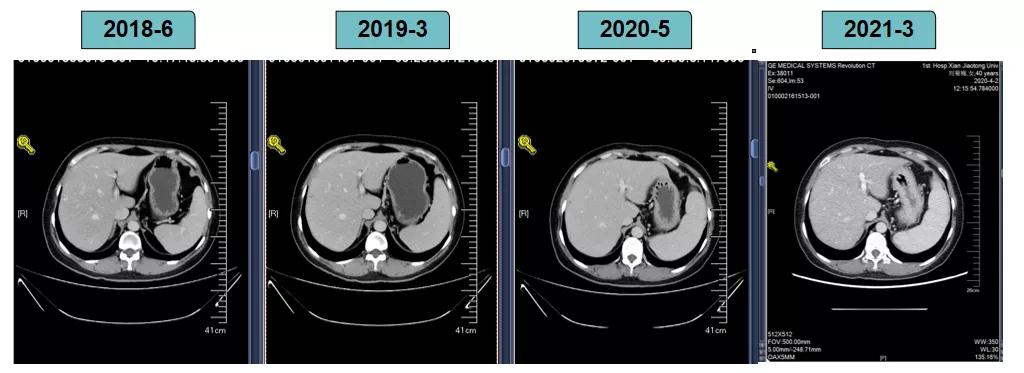

胸腹部增强CT示(2018-6-28):胸骨后占位,肝内异常强化灶,腹膜后肿大淋巴结。

靶病灶:腹主动脉左侧和下腔静脉右侧淋巴结

非靶病灶:肝左叶、肝右前叶下段;纵膈胸骨后淋巴结节;前上纵膈淋巴结;腹膜后小淋巴结

影像学评估-纵膈淋巴结:

影像学评估-肝脏:

影像学评估-腹膜后淋巴结: